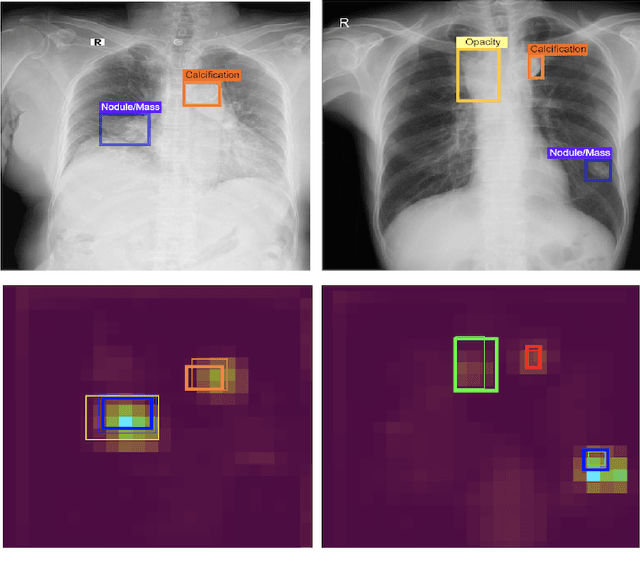

Abstract:Building an accurate computer-aided diagnosis system based on data-driven approaches requires a large amount of high-quality labeled data. In medical imaging analysis, multiple expert annotators often produce subjective estimates about "ground truth labels" during the annotation process, depending on their expertise and experience. As a result, the labeled data may contain a variety of human biases with a high rate of disagreement among annotators, which significantly affect the performance of supervised machine learning algorithms. To tackle this challenge, we propose a simple yet effective approach to combine annotations from multiple radiology experts for training a deep learning-based detector that aims to detect abnormalities on medical scans. The proposed method first estimates the ground truth annotations and confidence scores of training examples. The estimated annotations and their scores are then used to train a deep learning detector with a re-weighted loss function to localize abnormal findings. We conduct an extensive experimental evaluation of the proposed approach on both simulated and real-world medical imaging datasets. The experimental results show that our approach significantly outperforms baseline approaches that do not consider the disagreements among annotators, including methods in which all of the noisy annotations are treated equally as ground truth and the ensemble of different models trained on different label sets provided separately by annotators.